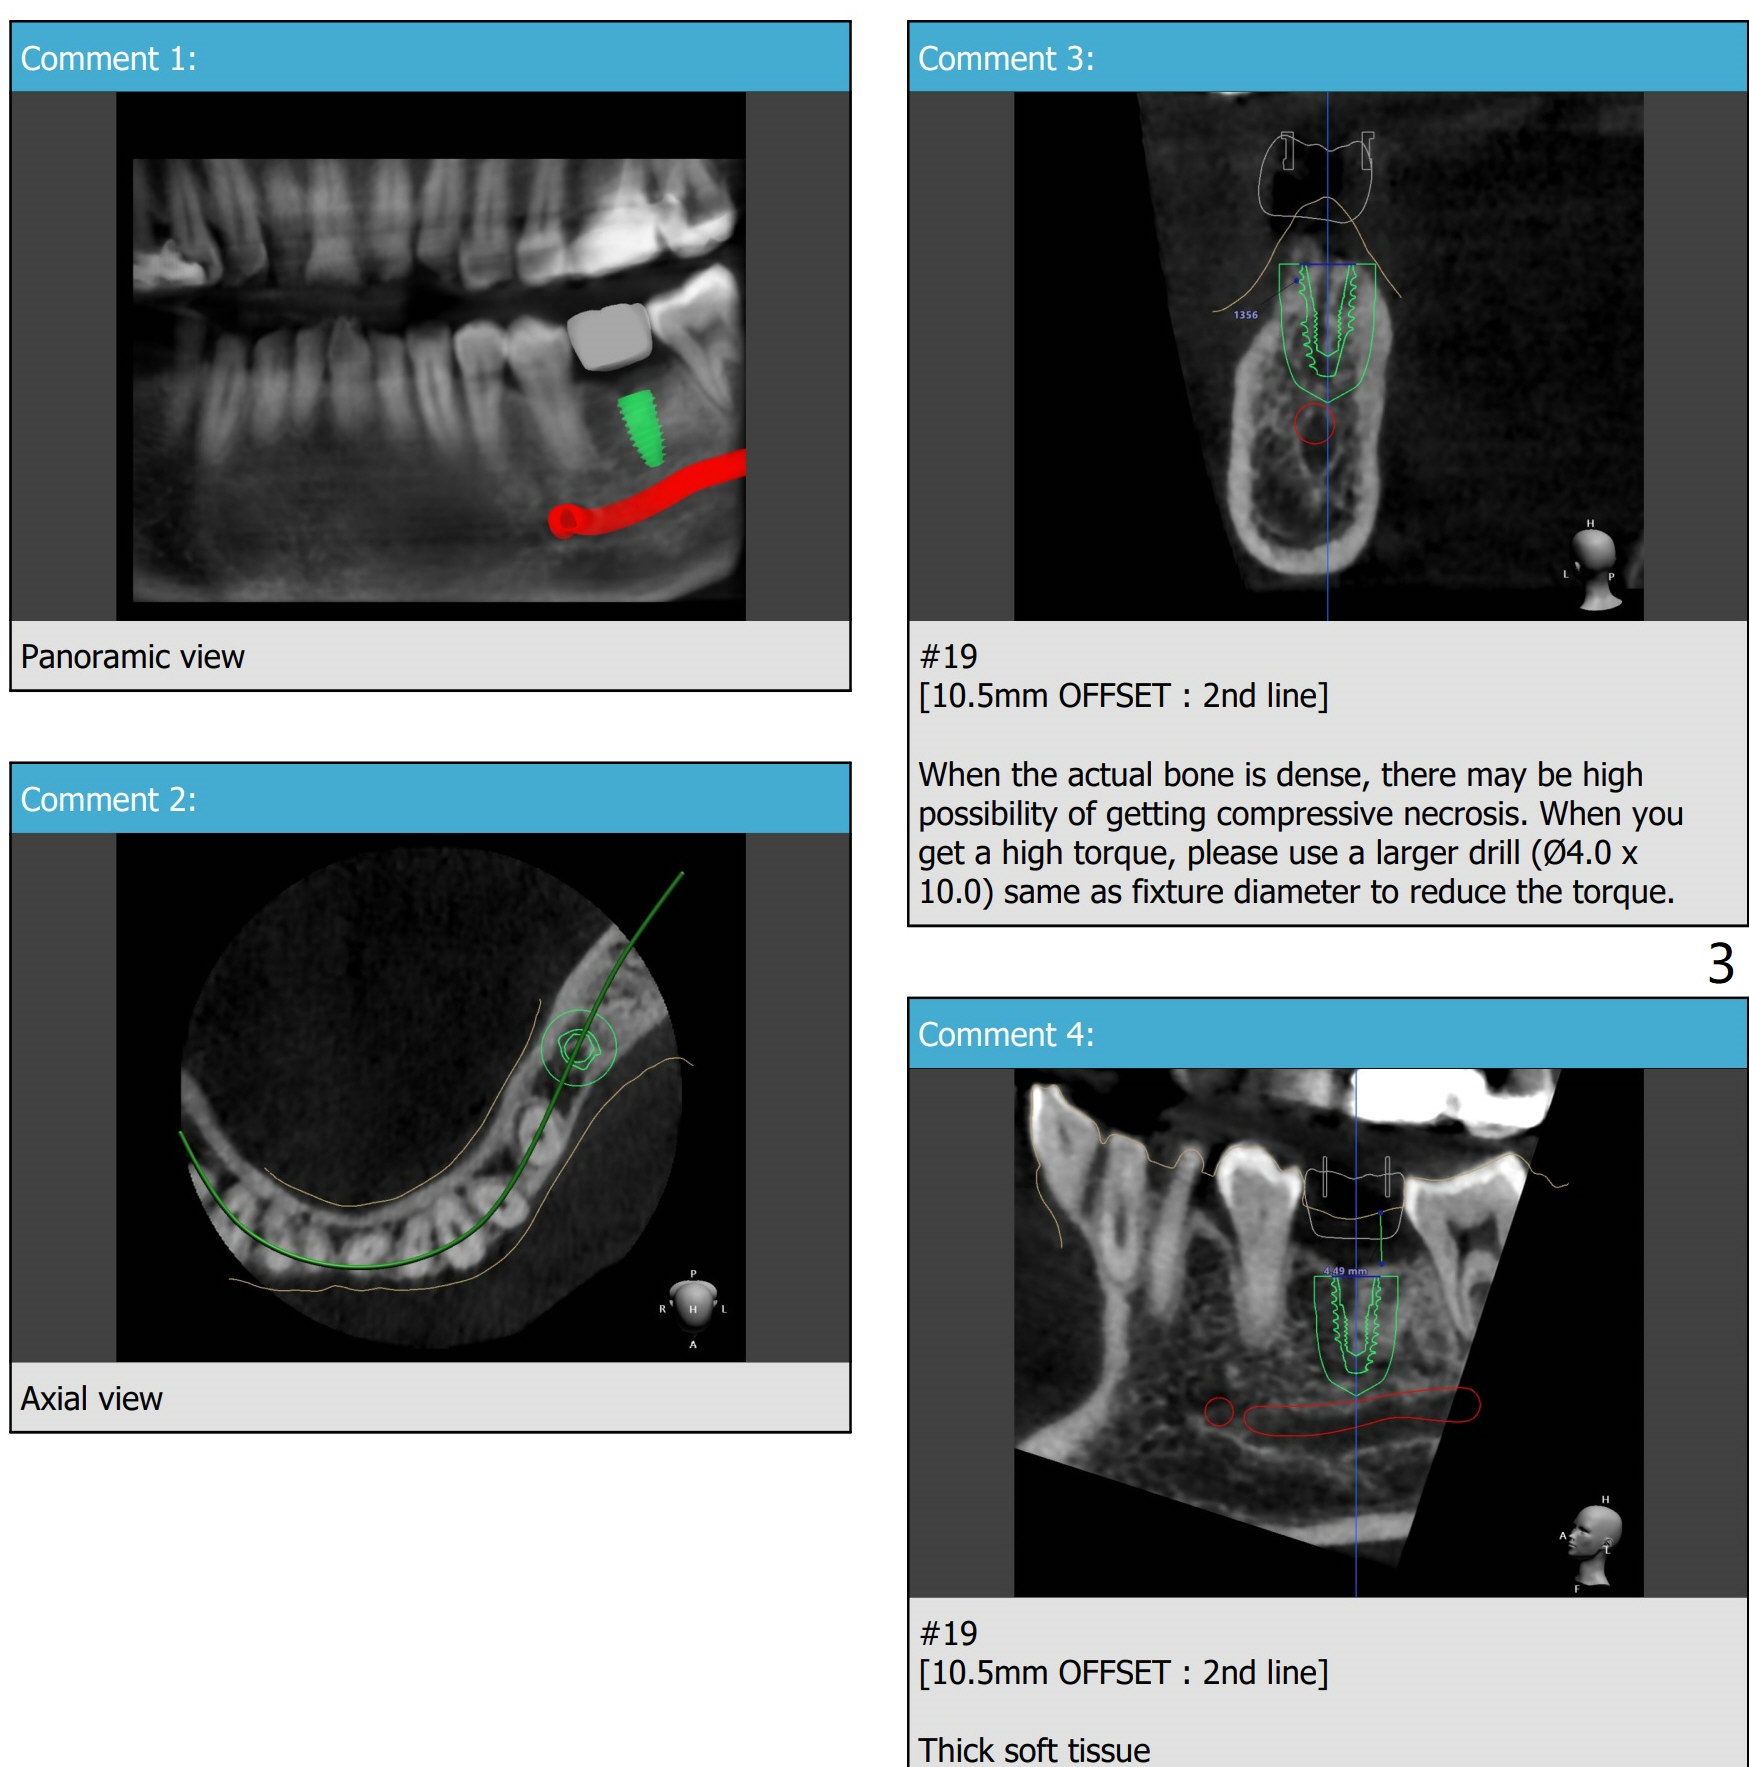

Short and Narrow, but Dense Ridge

A 64-year-old woman, diabetes, high cholesterol under control, + osteoporosis, taking med once a week. Ask the patient whether #18 RCT retreatment has been done by a specialist. If there is time, finish 9, 21,22 composite. Question: Is this guide made from scan or impression? What should be done before dipping the guide into Chlorhexidine? Since UF 3.8x8.5mm implant will be placed, change the last drill from 3.5x10 to 3.0x10 mm. Use 5.5 mm profile drill.